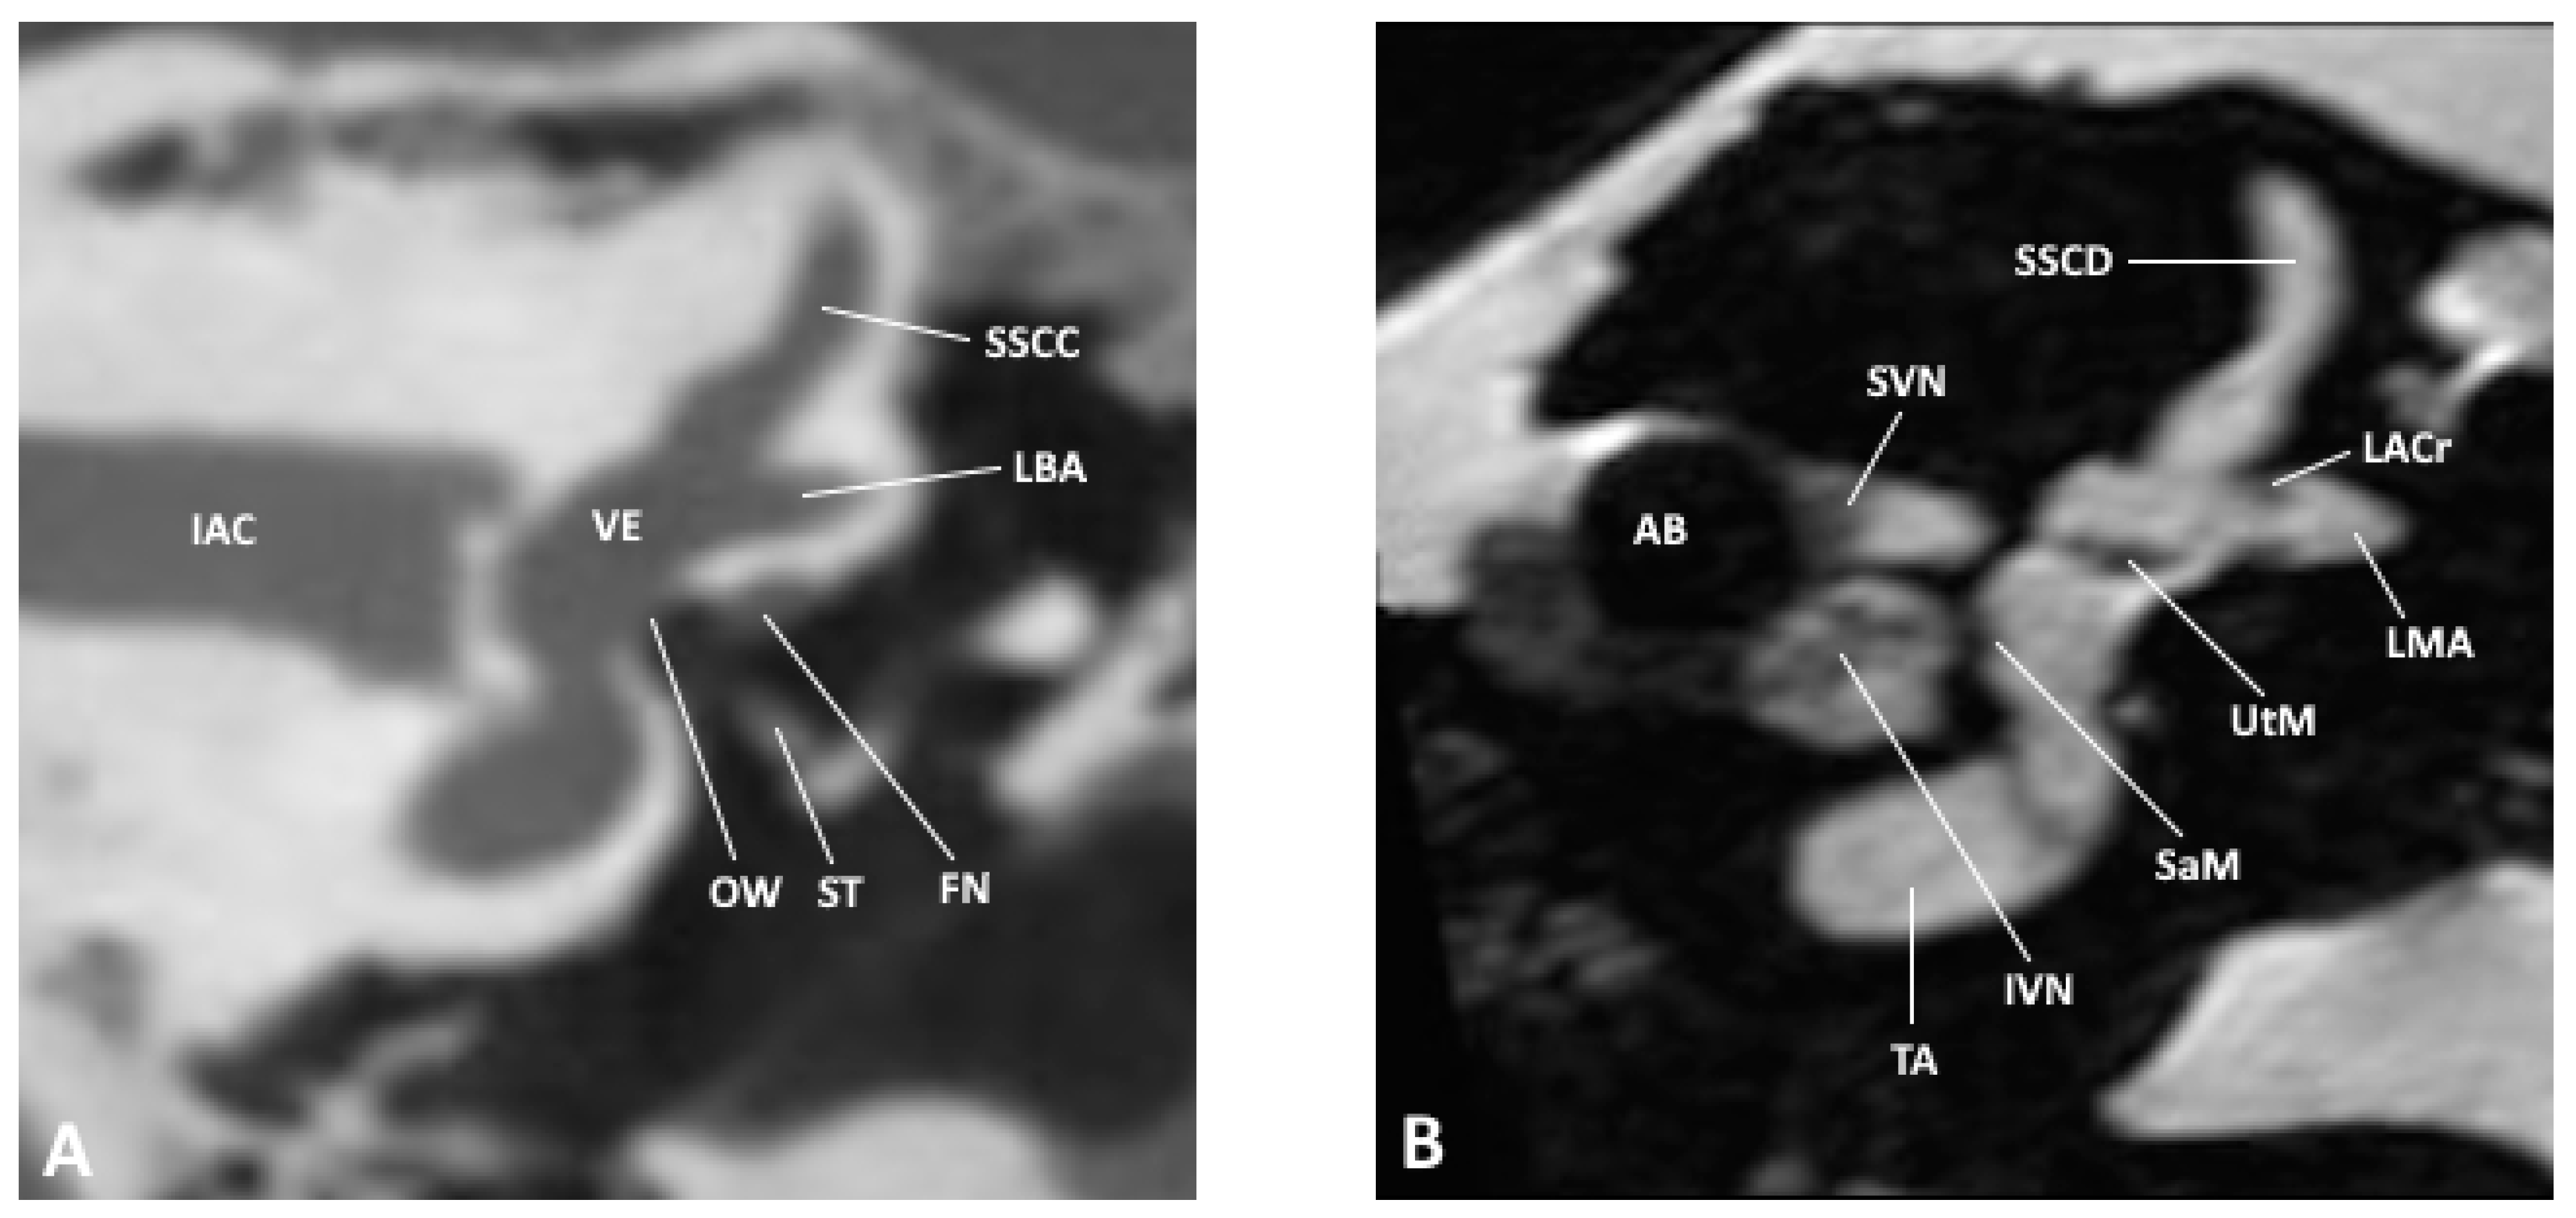

Figure 2. Coronal slice through the inner and middle ear at the level of the internal auditory meatus as observed by (A) CBCT and (B) MRI; AB, air bubble; FN, facial nerve; IAC, inner auditory canal; IVN, inferior vestibular nerve; LACr, lateral ampullary crest; LBA, lateral bony ampulla; LMA, lateral membranous ampulla; OW, oval window; SaM, saccular macula; SSCC, superior semicircular canal; SSCD, superior semicircular duct; ST, stapes; SVN, superior vestibular nerve; TA, truncation artifact; UtM, utricular macula; VE, vestibule.